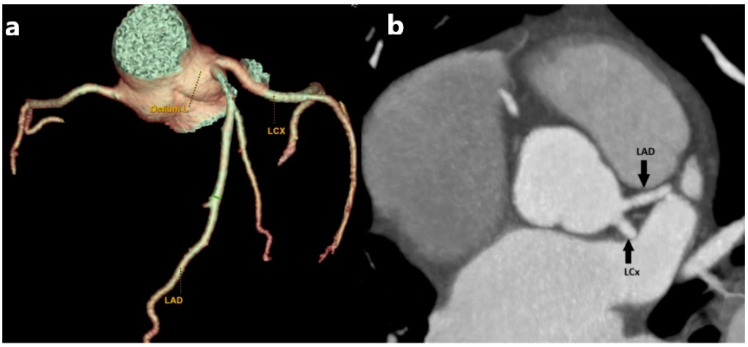

冠状动脉可在数量、起始点或路线上变化。这些变异属于冠状动脉解剖变异/异常的范畴,代表冠状动脉血管系统的先天性异常。通常,它们是良性的,无症状的,并且在为其他适应症进行冠状动脉造影时无意中被发现。然而,在某些情况下,异常的特征或其与周围结构的相互作用可能导致血流动力学紊乱。这些紊乱会导致血流紊乱,进而增加动脉粥样硬化和心肌缺血的可能性。如果有症状,潜在的表现包括胸痛、心律失常、晕厥、心肌梗死和心源性猝死。鉴于在某些情况下可能危及生命的并发症,早期和准确的诊断冠状动脉异常是至关重要的。用于评估冠状血管的最常用的诊断程序是冠状血管造影和多探测器行计算机断层扫描(MDCT)冠状血管造影。多层螺旋ct血管造影是一种无创、可靠、安全、灵敏的冠状动脉详细解剖可视化方法。它提供高分辨率成像,能够精确评估先天性冠状动脉变异,有助于临床决策和长期患者管理。我们进行了一项叙述性的回顾,分析和整合了大量关于冠状动脉变异和异常的文献。我们的目的是提供一个全面的,尽管不是详尽的,关于其定义、分类和MDCT血管造影检测的基本概念和发现的概述。通过整合MDCT成像的现有知识,我们寻求更好地理解冠状动脉变异的临床意义及其在心血管健康中的作用。

Coronary arteries may vary in quantity, point of origin, or course. These variations fall under the category of anatomical variants/anomalies of the coronary arteries, representing congenital abnormalities of the coronary vascular system. Generally, they are benign, asymptomatic, and identified inadvertently during coronary angiography conducted for alternative indications. However, in some cases, the anomaly's characteristics or its interaction with surrounding structures may cause hemodynamic disturbances. These disturbances can lead to turbulent blood flow, which in turn poses an increased likelihood for the development of atherosclerosis and myocardial ischemia. If symptomatic, potential manifestations include chest pain, arrhythmias, syncope, myocardial infarction, and sudden cardiac death. Given the potential for life-threatening complications in certain cases, the early and accurate diagnosis of coronary artery anomalies is of paramount importance. The most common diagnostic procedures used for the evaluation of coronary vessels are coronary angiography and multi-detector row computed tomography (MDCT) coronary angiography. MDCT angiography is a non-invasive, dependable, safe, and sensitive method for the detailed visualization of coronary anatomy. It offers high-resolution imaging that enables precise assessment of congenital coronary variations, aiding in both clinical decision-making and long-term patient management. We conducted a narrative review to analyze and integrate the body of literature on coronary artery varieties and anomalies. Our objective was to provide a comprehensive, albeit non-exhaustive, overview of essential concepts and findings related to their definition, classification, and detection with MDCT angiography. By integrating current knowledge in MDCT imaging, we seek to contribute to a better understanding of the clinical implications of coronary artery variations and their role in cardiovascular health.